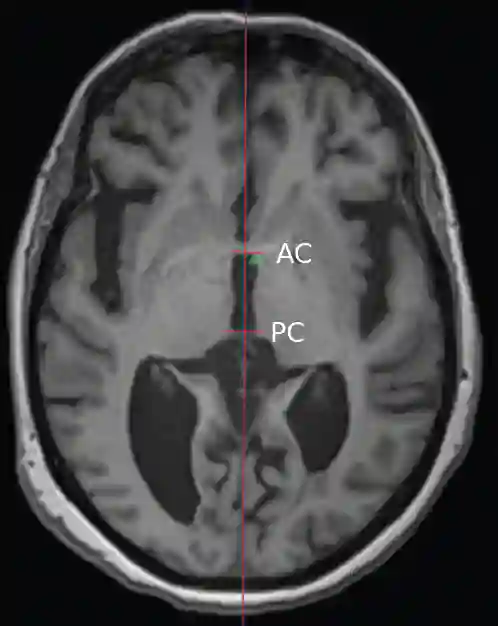

AC PC Linie axial

Darstellung der AC-PC Linie in einem axialen MRI Bild.